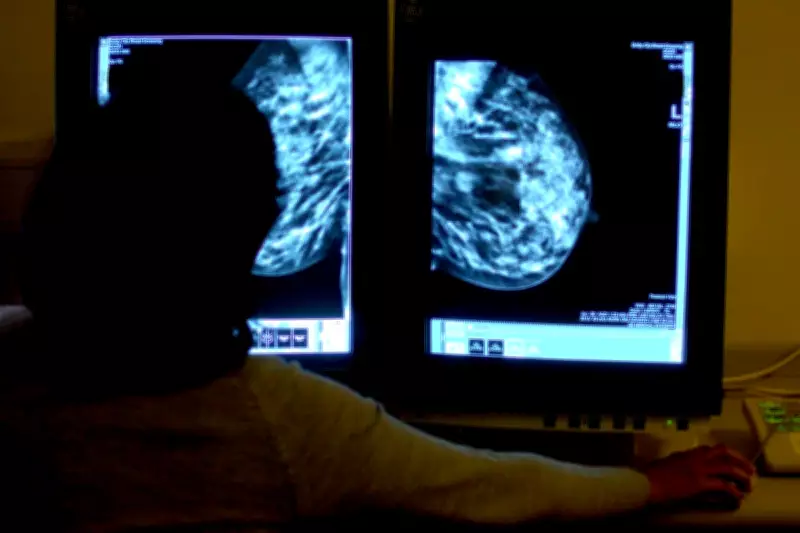

Bea Taylor, fellow at the Nuffield Trust think tank, contextualized the challenges: "The UK lags behind other countries in cancer outcomes and faces longstanding gaps in investment and staff, with key equipment like diagnostic scanners in short supply compared to countries like Germany, Sweden and Italy. These factors also made it more difficult for the NHS to recover cancer care post-pandemic."

She also highlighted potential technological solutions: "Taking advantage of new developments in digital technology could help, for example, by using AI to speed up diagnosis for patients, but making the UK 'world-leading' on cancer will take time and the commitment of scarce resources in a health service already under pressure."